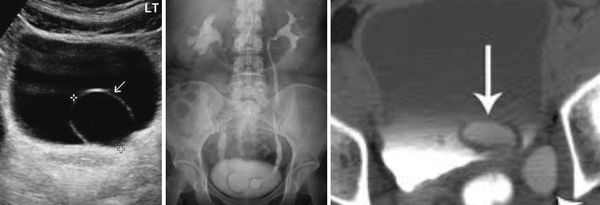

(Левый) На продольном трансабдоминальном УЗ срезе визуализируется небольшое уретероцеле с восходящей дилатацией мочеточника.

(Правый) На косопоперечном трансабдоминальном УЗ срезе визуализируется гиперэхогенный конкремент, вдавленный в правый пузырно-мочеточниковый сегмент (ПМС) с восходящей дилатацией мочеточника. Локальное выпячивание в интрамуральном отделе мочеточника соответствует псевдоуретероцеле.

(Левый) При микционной цистоуретрографии визуализируется округлый дефект наполнения в мочевом пузыре, указывающий на уретероцеле.

(Правый) На фронтальном Т2-взвешенном МР срезе визуализируется удвоенная система левой почки с расширенной верхней лоханкой и сдавливанием нижней лоханки/ Верхняя лоханка переходит в значительно расширенный и извитой мочеточник? оканчивающийся внутрипузырным уретероцеле.